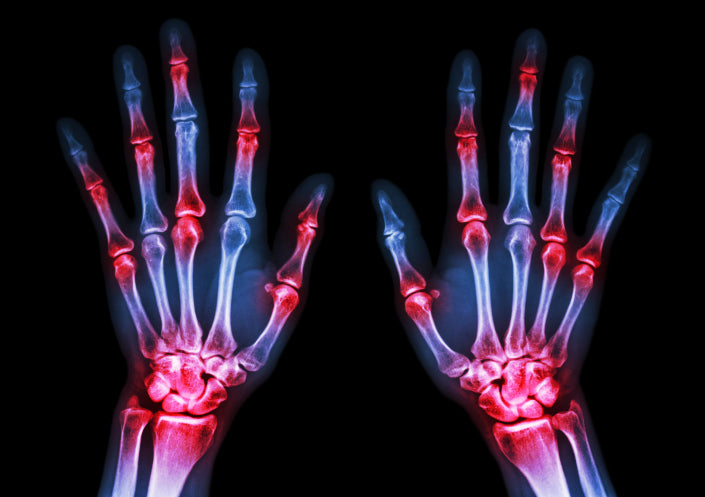

Are You Tired Of Arthritis Pain?

Arthritis is the top cause of disability in the...